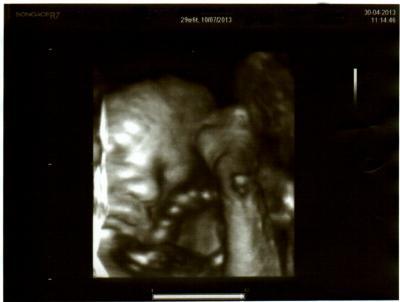

Außerdem hab ich mir heute mal noch den Luxus eines zusätzlichen 3D Ultraschalls geleistet. Da ja sowieso ein Ultraschall anstand.

Hier also noch ein Bildchen von unserem Zwerg.

Man sieht das Gesicht, neben der Wange ist die Nabelschnur und dann sieht man einen Fuß. (Lag also total zusammengeklappt im Bauch )